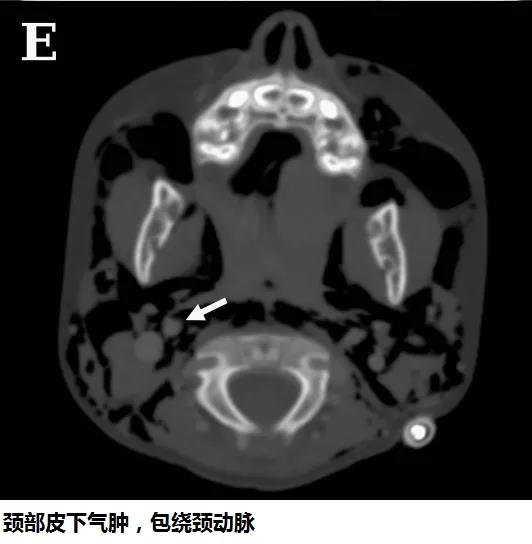

頭顱、胸部CT提示廣泛皮下氣腫、縱隔氣腫、心包積氣、甚至眼眶周圍都積氣,眼球突出!頸部無感染征象,腸管無破裂征象,看來氣體還是來自肺部。但是,肺部無感染、無肺大泡、無劇烈咳嗽,只有間質性肺氣腫。縱隔氣腫、皮下氣腫的治療,核心是根除病因,切開引流效果不像氣胸那么理想,而且縱隔切開引流還存在手術風險。找不到病因,如何是好?考慮患者是過敏體質,有皮疹,繼續(xù)呼吸機輔助呼吸,先治療過敏,肌肉注射腎上腺素、靜脈注射類固醇激素和抗組胺藥、吸入支氣管擴張劑等。經上述治療,臨床表現(xiàn)和影像學方面都有迅速的改善。隨后拔出氣管導管,口服類固醇激素出院,門診隨訪。